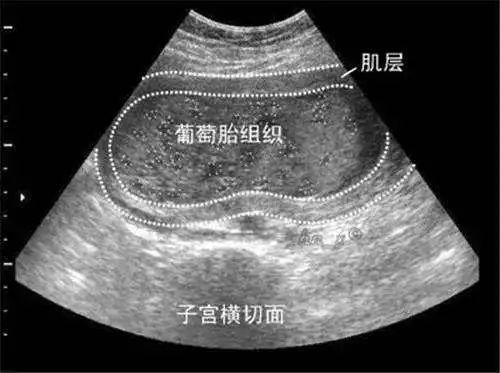

葡萄胎是指怀孕后滋养细胞不规则增生、绒毛间质水肿,每一个水泡,就是一根水肿的绒毛,许多水泡连在一起,看上去就像一串串葡萄,因而称之为葡萄胎。

经检查,医生发现验血报告显示血清中HCG浓度大大高于正常妊娠时相应月份值,彩超提示宫内无孕囊及胎心,有雪花状阴影,考虑为葡萄胎。医生建议澜澜进行清宫,否则再发展下去,将影响母体安危。第二天,医生就为澜澜进行了清宫手术。

葡萄胎一般在怀孕40~50天左右到医院做B超就可以发现,停经后阴道流血是葡萄胎最早和最常见的症状,发生率一般在98%以上。